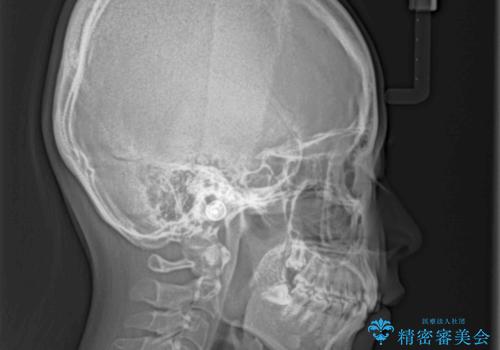

- 口元のデコボコと深い咬み合わせ(ディープバイト)を気にして来院された患者様です。

インビザラインによる上下歯列の拡大と、IPR(歯と歯の間を削る)にるスペースの獲得により、口元のデコボコとディープバイトを改善することとしました。